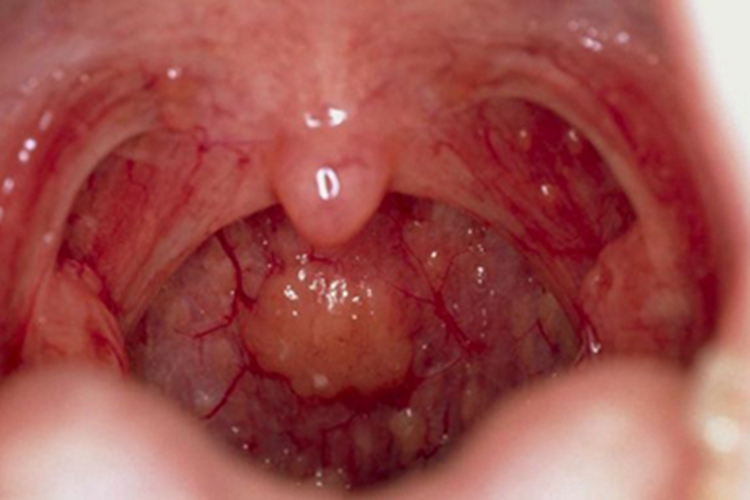

慢性咽炎患者在进行检查时,可见局部黏膜充血、增厚,有血丝,同时淋巴滤泡显著增生,形成大小不定的包块。患者可有咽部异物感、痒感、干燥感等不适。